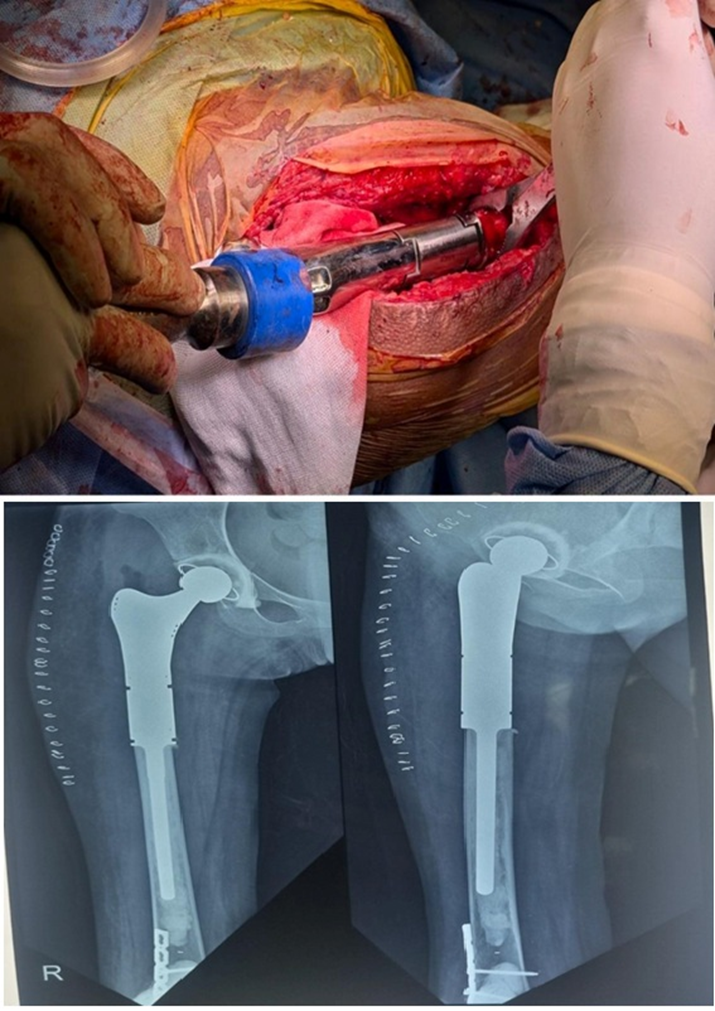

The proximal femoral GCT was excised and reconstructed using a proximal femoral mega prosthesis (Fig. 4).

Figure 4: Mega prosthesis of the proximal femur after excision of the tumor.

The distal femoral lesion was treated with curettage and bone cement filling (Fig. 5). In addition, a plate was applied at the distal femur for reinforcement. The patient was allowed to bear weight with a walker 21 days postoperatively. Gradually, she demonstrated significant clinical improvement, regaining the ability to bear weight without pain or support. A repeat HRCT of the chest showed regression of the small lesions. Postoperatively, denosumab was continued for 4 months as a monthly dose. Follow-up imaging over 12 months revealed no evidence of recurrence, and laboratory parameters remained within normal limits (Fig. 6).

Figure 6: 1-year follow-up of the case showing no recurrence with good fixation.